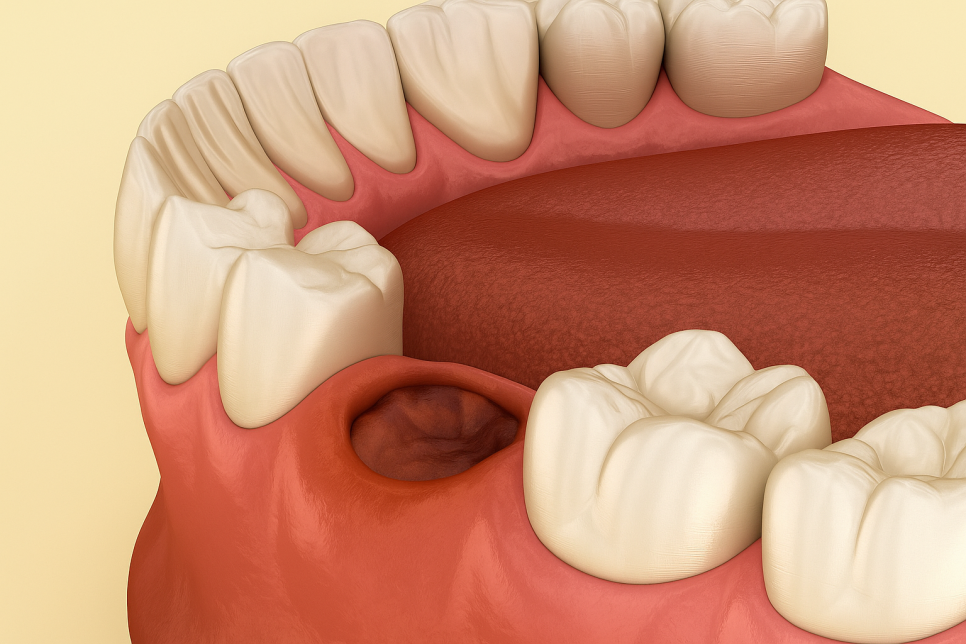

텅 빈 공간이 되어있는 그 부위는

혈병(피딱지)가 형성되며

치유 과정에 들어가게 됩니다.

하지만 이것이 제대로 유지되지 못할 경우

드라이 소켓(Dry Socket)이 생길 수 있는데,

이것이 바로 심한 통증과 염증을 초래하는

주 요인 중 하나라고 할 수 있습니다.